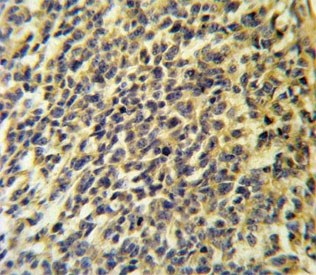

IHC testing of FFPE human testis carcinoma tissue with CaI-PLA2 antibody. HIER: steam section in pH6 citrate buffer for 20 min and allow to cool prior to staining.